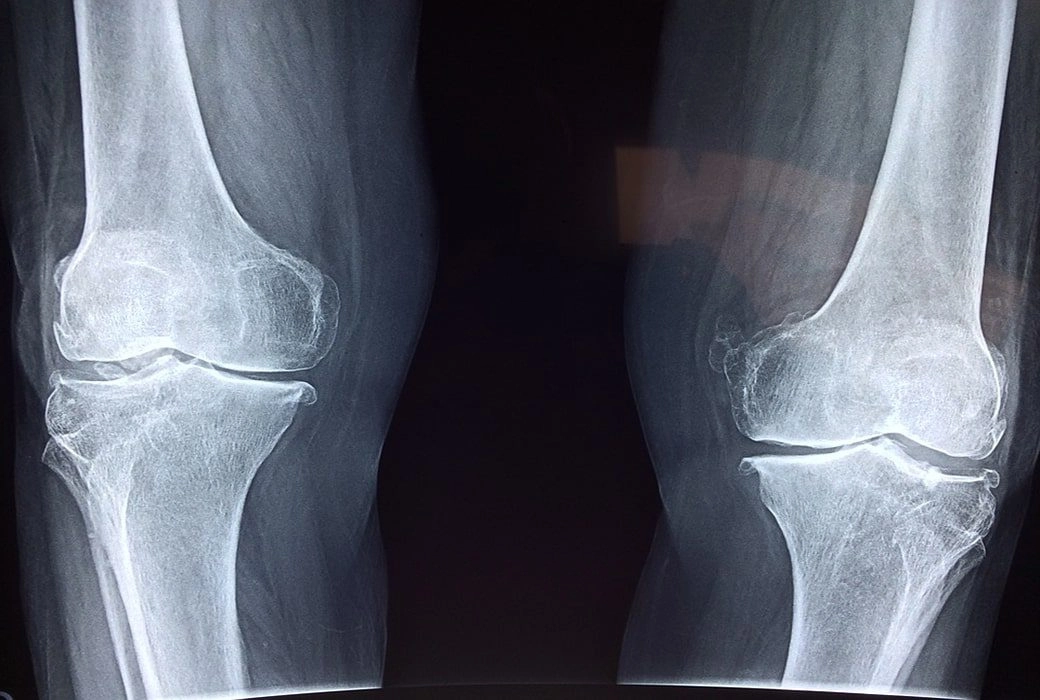

1. Prepatellar Bursitis

Prepatellar is an inflammation of the bursal sac situated between the overlying skin and the patella. The most popular cause is trauma due to a fall or direct pressure and friction of repetitive kneeling. This is one of the types of bursitis that may become infected.

The diagnosis of prepatellar is normally not difficult. Swelling occurs superficial to the patella, and effusion may or may not appear. The range of motion is reasonably painless. A patient may complain of knee swelling and knee pain just over the front of the knee.